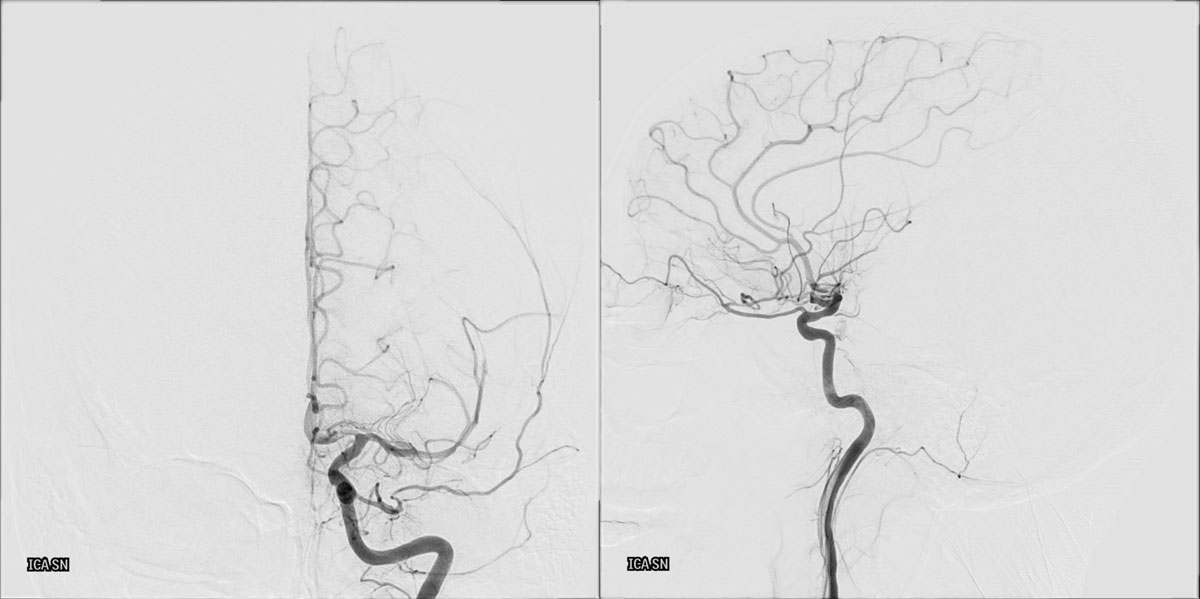

DSA

L - ICA

VASO-CT post

6 months DSA follow up